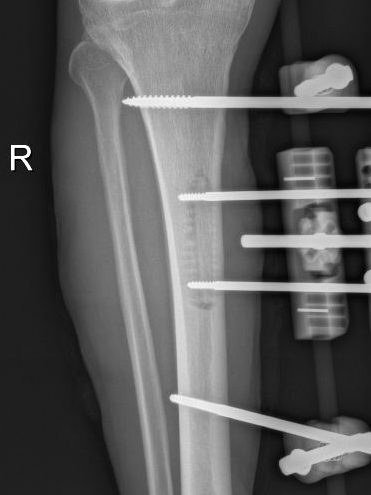

2025年11月1日,由遵义市医学会手外科分会主办、遵义市第二城市医疗集团(贵州航天医院)承办的遵义市医学会手外科分会学术交流会暨贵州省继续医学教育项目《急诊手外伤治疗临床研究新进展专题研讨班》在贵州航天医院成功举办,汇聚了遵义市手外科领域专家及基层医疗骨干,通过专题研讨与临床经验分享,共探急诊手外伤诊疗新进展。 会议特邀遵义市医学会手外科分会主任委员金文虎教授,遵义市医学会手外科分会副主任委员张子阳教授,遵义市医学会手外科分会常务委员杨绍浦教授,贵州航天医院陈明勇教授、赵兴东教授等遵义市手外伤专家进行交流分享;贵州航天医院党委委员、副院长彭亮参加会议并致辞,贵州航天医院骨科医务人员,遵义市第二城市医疗集团成员单位及红花岗区、绥阳县、桐梓县等区县医疗机构手外伤骨干参与。 贵州航天医院党委委员、副院长彭亮致辞 学术交流 本次学术交流以“急诊手外伤治疗临床研究新进展”为主题,通过理论授课与临床案例结合,共同探讨急诊手外伤临床诊疗全链条诊疗策略、关键技术、临床研究新进展,促进规范化诊疗技术向基层下沉,助力提升区域手外伤应急处置与修复能力。 贵州航天医院赵兴东教授分享《急诊手外伤的诊断与治疗原则》 贵州航天医院陈明勇教授分享《开放性骨折的治疗原则》 贵州航天医院张军教授分享《甲沟炎Winograd手术的临床应用》 贵州航天医院赵兴东教授分享《手部常见的皮肤缺损及治疗原则》 贵州航天医院张艳金教授分享《开放性骨折的清创术》 贵州航天医院冷家雄教授分享《下肢创面修复的常用皮瓣之股前外侧皮瓣》 贵州航天医院邬夏荣教授分享《踝关节慢性不稳的诊治》 贵州航天医院卢懿明教授分享《掌骨骨折》 贵州航天医院张艳金教授分享《手部肌腱的解剖与修复方法》 本次研讨班为遵义市手外科领域医务人员提供了深度交流契机,强化了医疗机构间的协作网络,进一步推动学科创新与临床实践融合,为健康遵义建设注入新动能。 贵州航天医院骨科专家简介 陈明勇 骨一科主任,副主任医师 临床擅长:从事创伤骨科工作约20年,对骨缺损、骨不连、骨肿瘤、肢体畸形等的肢体矫形重建及功能重建,慢性化脓性骨髓炎的根治治疗、糖尿病足的保肢治疗、快速康复理念(ERAS)下的老年骨折的诊治,四肢复杂骨折的诊治,四肢骨折等微创手术治疗具有丰富的临床经验。 2004年毕业于遵义医学院临床专业,曾在中国人民解放军总医院、广西医科大学第一附属医院、上海第六人民医院骨科进修。中国中西医结合学会骨伤科专业委员会横向骨搬移治疗糖尿病足及微血管网再生学组首届委员,遵义市医学会创伤分会常务委员。 瞿 晖 骨科党支部书记,骨二科主任,副主任医师 临床擅长:对骨科的常见病、关节外科、脊柱外科及运动医学疾病的诊治具有丰富的临床经验,熟练掌握骨科手术操作技术。 毕业于遵义医学院临床医学系,2005年前往广州中山大学第一附院骨显微医学部进修学习,2011年前往成都华西医院进修学习,并多次在省内外学习骨科相关知识,是中华医学会骨科分会会员。 赵小锋 中共党员,骨二科副主任,副主任医师 临床擅长:从事骨科临床工作11年,对骨科常见病、多发病诊疗有较为丰富的临床经验,擅长脊柱相关疾病诊断及治疗,尤其是颈、腰、腿疼痛疾病诊断及治疗,擅长胸腰椎骨折微创经皮穿刺内固定术、经皮穿刺椎体成形术、经皮穿刺脊柱内镜下腰椎间盘摘除术、单纯开创腰椎间盘摘除术、腰椎滑脱复位椎间植骨椎融合内固定术、腰椎管狭窄减压融合内固定术及人工髋、膝关节置换术等。 2012年毕业于遵义医学院外科学专业硕士研究生,2019年参加“遵义市115医学人才精英计划”于上海交通大学第一附属医院培训学习,2023年于北京大学第三人民医院脊柱外科进修学习,曾获得遵义市优秀医师荣誉称号。 遵义市手外科第一届委员,遵义市医学会创伤分会第一届委员,遵义市医学会创伤分会第二届委员,贵州省康复医学会第三届脊柱脊髓专业会委员,遵义市医学会烧伤与整形外科学分会委员,发表论文5篇,其中国家级核心期刊1篇,SCI论文1篇,主持市级课题1项并结题,参与市级课题2项。 赵兴东 骨科主任医师 临床擅长:擅长骨科的常见病及各种创伤、四肢骨折创伤修复、骨感染、手足疾病的诊治和手足体表畸形的矫形整复,熟练掌握骨科四肢骨病及创伤的手术操作技术,尤其在四肢关节复杂性损伤、手足外伤、组织缺损创面、难治创面的皮瓣修复方面及平足、高弓足矫形方面及四肢慢性疼痛诊治、康复方面具有丰富的临床经验。 硕士研究生,毕业于遵义医学院临床外科系,2015年前往山东省立医院手足外科进修学习;遵义市医学分会创伤分会第一、二届委员,遵义市手外科医学会第二委届员会常务委员;在省级及省级以上期刊发表文章9篇,参编著作2部,参与主持并完成市级课题1项,参与市级课题2项、省级课题1项。 张艳金 中共党员,骨科副主任医师 临床擅长:从事骨外科工作16年,对复合伤、多发伤的救治、四肢骨干骨折、关节周围骨折、骨肿瘤、骨髓炎等诊治具有丰富的临床经验。 中共党员,硕士研究生,2006年本科毕业于山西医科大学第二临床医学院,2011年研究生毕业于北京军区总医院;在“老年COPD患者合并髋部骨折的诊治”国际合作课题组研究两年,在老年髋部骨折的诊治方面具有丰富的经验,并发表论文6篇;主持遵义市级课题1项,承担遵义医科大学的临床教学工作,获得遵义医科大学优秀带教老师荣誉。编撰有《骨科疾病诊疗精粹》一书,开展2项新技术,编撰地方规范《务川自治县创伤骨科常见疾病诊疗规范》一书。 张俊凯 骨科副主任医师 临床擅长:从事骨科临床工作28年,对创伤骨折、骨感染、骨缺损、骨不连等外科诊治,四肢骨折的微创手术治疗,四肢复杂骨折(如关节内粉碎性骨折、多发骨折等)的损伤控制及手术治疗等具有丰富的临床经验。 1995年毕业于遵义医学院临床专业,2009年前往复旦大学附属医院骨科进修1年。 卢懿明 中共党员,骨科副主任医师 临床擅长:从事骨科工作18年,对创伤骨折、四肢骨折的微创手术治疗、四肢复杂骨折(如关节内粉碎性骨折、多发骨折等)的损伤控制及手术治疗,尤其是髋部骨折的PFNA等微创技术,踝关节骨折、膝关节周围骨折的Mipo微创技术等具有丰富的临床经验,开展了4项新技术,发明6项新型专利技术。 2005年毕业于遵义医学院临床专业,2017年,前往南方医科大学第三附属医院骨科进修半年,回院后运用Mipo技术对骨干骨折及干骺端骨折的治疗技术,同时积极开展骨盆骨折、髋臼骨折腹直肌外侧切口的应用;发表了多篇专业论文,经常参与省内外学术交流会授课,获得医院荣誉称号多个。 邬夏荣 骨科副主任医师 临床擅长:从事骨科工作16年,对四肢复杂骨折、骨肿瘤的诊治,尤其是足踝创伤、慢性踝关节损伤、平足症等诊疗具有丰富的临床经验。 2006年毕业于遵义医科大学临床医学专业,曾在陆军军医大学西南医院进修学习,发表多篇骨科学术论文。 余德怀 中共党员,骨科副主任医师 临床擅长:从事骨科工作10余年,对运动医学、骨关节、脊柱外科常见病、多发病的诊治具有丰富的临床经验。 硕士研究生,2011年毕业于遵义医学院临床医学专业,曾前往遵义医科大学附属医院运动医学专业进修学习;是贵州省医学会运动医学分会青年委员,西部关节镜联盟委员;发表多篇骨科学术论文。 冯 乾 骨科副主任医师 临床擅长:从事骨科工作近20年,熟练掌握骨科多发病及常见病的诊治,尤其对脊柱退变性疾病的诊断及治疗具有丰富的临床经验,主要研究脊柱微创相关治疗方式,能熟练开展椎间孔镜及UBE。 曾前往北京大学第三医院进修学习疼痛及椎间孔镜、首都医科大学友谊医院专业进修脊柱内镜;是贵州省康复医学会第三届脊柱脊髓专业委员会委员;发明专利3项、发表脊柱外科专业论文多篇。 贵州航天医院骨科简介 基本情况 贵州航天医院(原3417医院)骨科组建于1968年,前身是以创伤和断肢(断指)再植闻名于世的上海市第六人民医院骨科,中国断肢(断指)再植的奠基者、中科院院士陈仲伟等专家莅临科室指导医疗和教学,并在70年代开展了贵州省首例断肢(断指)再植手术。组建50余年来,诊治患者已逾百万,挽救了无数的伤病员,成为了保障遵义地区人民群众健康的重要支撑。 经过几代人的不懈努力,今天的骨科,已由创伤骨科发展至骨病、骨肿瘤、骨结核等领域,现有脊柱外科、关节外科、四肢创伤、手足外科四个亚专科,成为了集医疗、教学、科研于一体的综合学科,是贵州省临床重点专科、遵义市临床重点专科、遵义市骨科临床医学中心、遵义市基层骨科专科联盟理事长单位。 科室目前开放床位110张,共有医护人员50余人,副高级以上专家18人,硕士研究生15人。拥有一流骨科医疗设备多台,每年不定期选派优秀技术骨干到全国各大知名医学院校进修、学习、参观、交流,并邀请国内、国外知名专家教授来院进行交流、指导,通过不断引进国内外先进的诊疗技术,科室医疗技术水平稳步提升,为广大人民群众提供了优质的医疗服务。 专科特色 骨一科 (一)骨缺损、骨不连的肢体与功能重建 胫骨横向骨搬移技术治疗糖尿病足: (二)慢性骨髓炎的根治治疗 (三)肢体缺血性疾病如糖尿病足、脉管炎的保肢治疗 (四)皮瓣修复 (五)复杂创伤的治疗 (六)老年髋部骨折及小儿骨折快速手术 老年髋部骨折: 骨二科 (一)胸腰椎骨折微创经皮椎弓根螺钉固定术 (二)老年性骨质疏松性患者腰椎滑脱脊柱内固定术(骨水泥螺钉) (三)V形双通道脊柱内镜技术(VBE)腰椎融合术治疗腰椎退行性疾病 (四)老年性骨质疏松性骨折(PVP/PKP)术 (五)人工髋关节置换术 (六)双侧股骨头坏死人工全髋关节置换 (七)右侧全髋置换术后假体周围骨折翻修 (八)人工膝关节置换术 (九)人工膝关节假体松动翻修 (十)关节镜技术 传统手术切口 关节镜技术切口 诊疗范围 骨一科 1.四肢创伤、矫形。 2.手、足踝外科。 骨二科 End